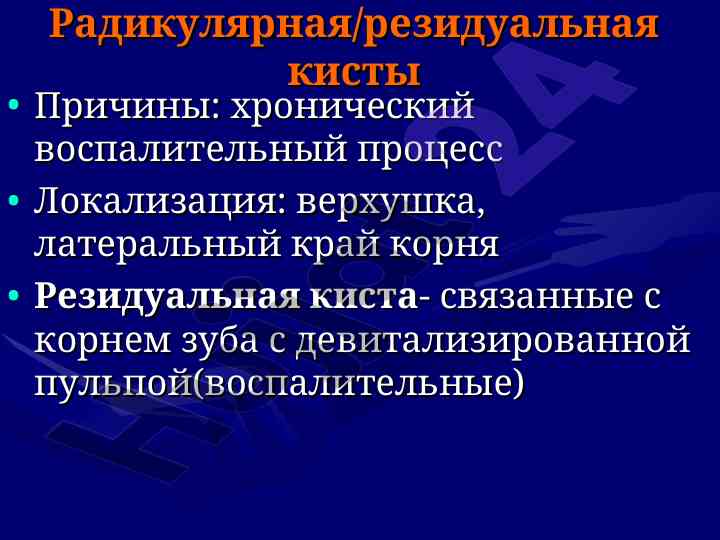

Данная лекция охватывает диагностические критерии, локализацию и структуру кист и опухолей челюстно-лицевой области, включая одонтогенные и неодонтогенные кисты.